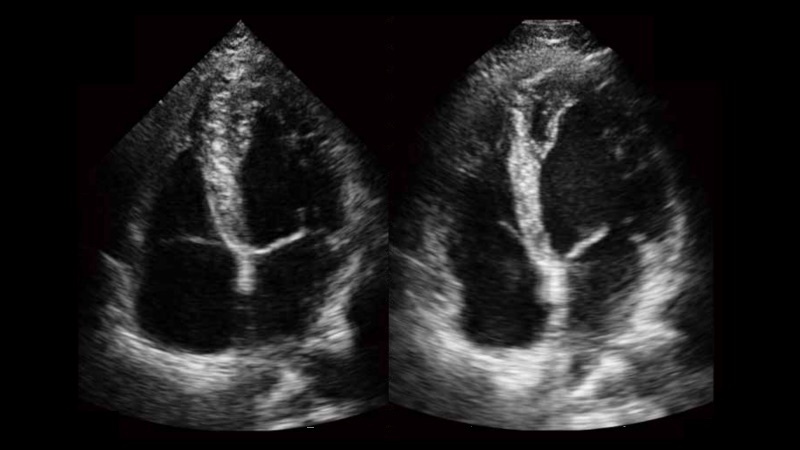

新一代微米成像技術(shù)大大提高了器官和病變的可見性。高清對比度分辨率將抑制斑點噪聲,同時保持真實的組織結(jié)構(gòu)。